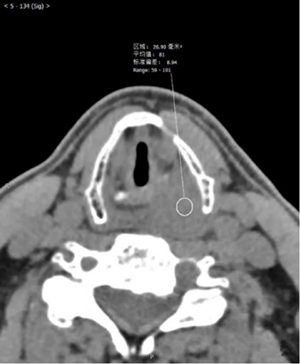

影像图片

评论: 声门上层面喉左后壁增厚,呈软组织密度肿块影,边界不清,左侧杓状软骨大部分显示不清,左侧甲状软骨边缘毛糙,增强扫描呈渐进性轻度强化。